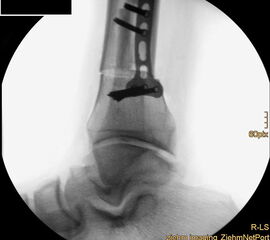

Wir benutzen zur Osteosynthese 3,5 mm LCP T-Platten. In der intraoperativen Röntgenkontrolle kann im seitlichen Bild die Zentrierung des Talus überprüft werden, und ggf. durch eine milde extendierende oder flektierende Korrekturkomponente verbessert werden 18. Eine begleitende Deformität der Fibula korrigieren wir üblicherweise mit einer z-förmigen Osteotomie die wir mit einem 1/3 Rohrplättchen sowie einer Zugschraube sichern 18.